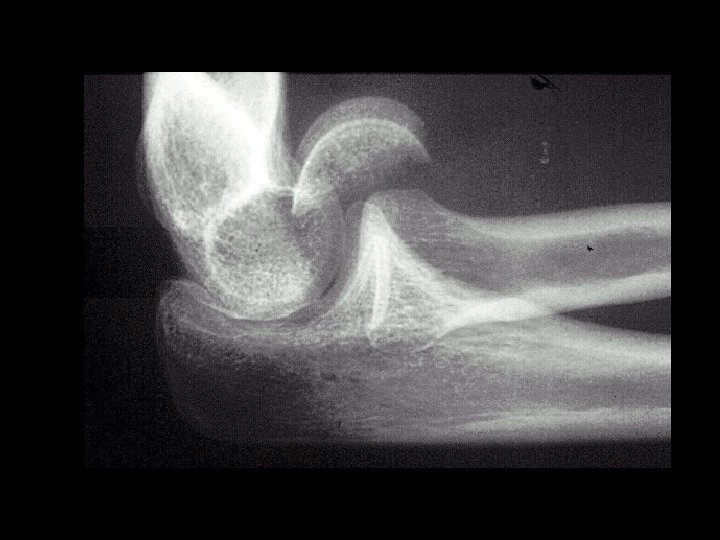

Capitellum fracturedislocation • Findings: – fracture-dislocation of the capitellum – due to direct trauma – second most common site in kids (most common is suprcondylar) • ddx: – NONE! – This is an Aunt Minnie!